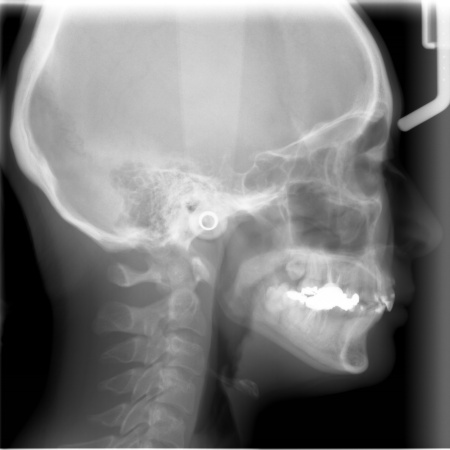

レントゲン撮影をして詳しく調べた結果、歯の位置だけでなく、骨格的な問題があることが分かりました。

患者様の場合、骨格的な上顎前突が噛み合わせを乱している主な原因であることから、矯正治療では前歯を後方へ大きく動かすためのスペースを確保する必要があります。